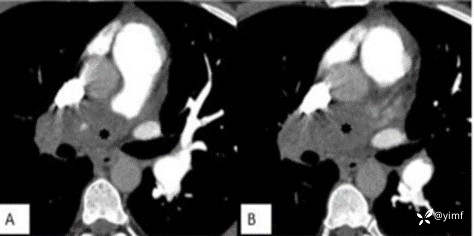

既往史:患者5年前因坐火车长达12个小时,腿部血液流通不畅进而形成下肢深静脉血栓(DVT),此后规律口服了6个月的利伐沙班进行抗凝治疗。此后没有进一步调查血栓形成原因,因无不适症状未服任何抗凝药物。4年前患者因呼吸困难,行相关检查示肺栓塞(相关影像学资料见图1A-C),并进行了紧急溶栓治疗。在此之后,他接受了利伐沙班治疗,并继续服用至今。

图1 CT肺动脉造影(CTPA)

图2 CT肺动脉造影显示右肺动脉有残余慢性血栓,主肺动脉扩张